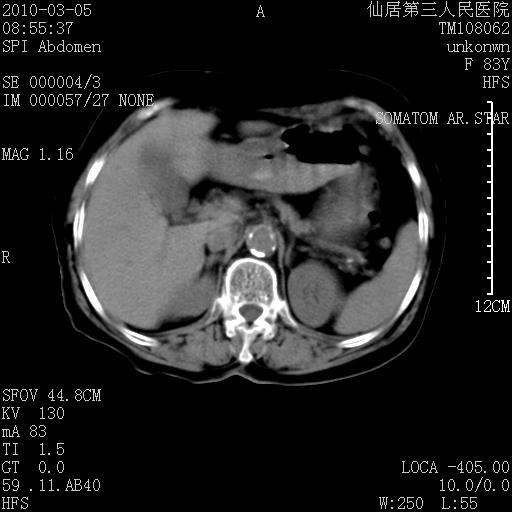

标题: CT24879:腹直肌病变。在线等。 [打印本页]

标题: CT24879:腹直肌病变。在线等。

女性,83y,腹痛一周。

考虑:左侧腹直肌神经纤维瘤可能

神经纤维瘤—伴有出血?

有无外伤,血肿或韧带样瘤

考虑左侧腹直肌血肿,肿瘤性病变待排。

增强看看,mfh可能性大,次之可考虑血肿、bfh、转移瘤、神经纤维瘤、侵袭性韧带样纤维瘤等。肝内钙化灶,右肾结石。

血肿,纤维瘤,子宫内膜异位都有可能。